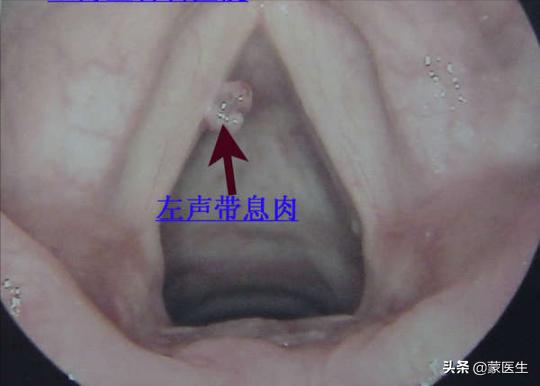

声帯ポリープ

暴露される可能性が最も高いのは声帯ポリープ声帯にポリープができると、声がかすれ、病院を受診することになる。喉頭鏡検査一般的にはインゲン豆かピーナッツくらいの大きさである。

なぜ声帯ポリープができるのか?

理由としては、不適切な声の使い方や悪い発音の癖、上気道炎、鼻炎、咽頭炎を繰り返していること、長期にわたるタバコやアルコールの刺激、特に女性は受動喫煙が多いこと、過労、徹夜による不健康状態などが挙げられる。

一般的に、安静にしていれば、声帯ポリープは消える。

しかし、声帯ポリープが癌化する可能性はありますが、その確率は比較的低いです。声帯ポリープが癌化するのを防ぐためには、診断後できるだけ早く治療する必要があります。声帯ポリープの主な治療法は手術による切除で、ほとんどのポリープは顕微鏡下で切除することができます。

手術後の声帯ポリープの再発を防ぐためには、声の保護に気を配り、大きな声を出さないようにし、辛いものや刺激の強いものを食べないようにする必要があります。